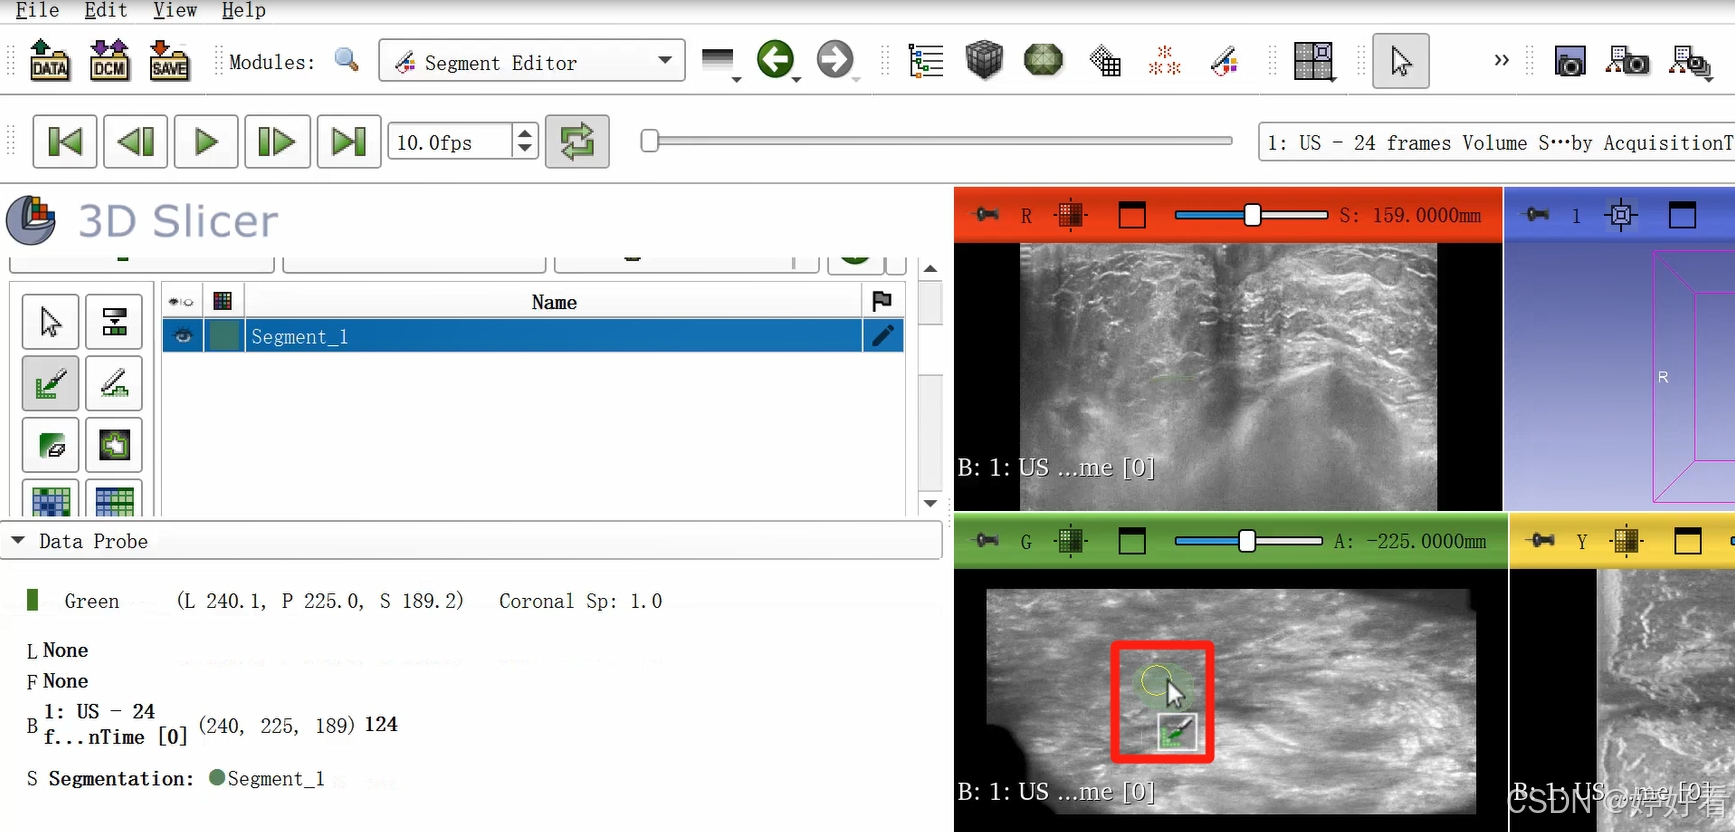

2.3 使用Paint功能勾画感兴趣区域。

可以隔两三层画一次(示例中为随意勾画,大家在实际操作中可以请专业的医生确认感兴趣区域)。

这是一个三维的图像,我们只要在一个面上勾画就可以了,另外两个面会自动显示勾画的区域。